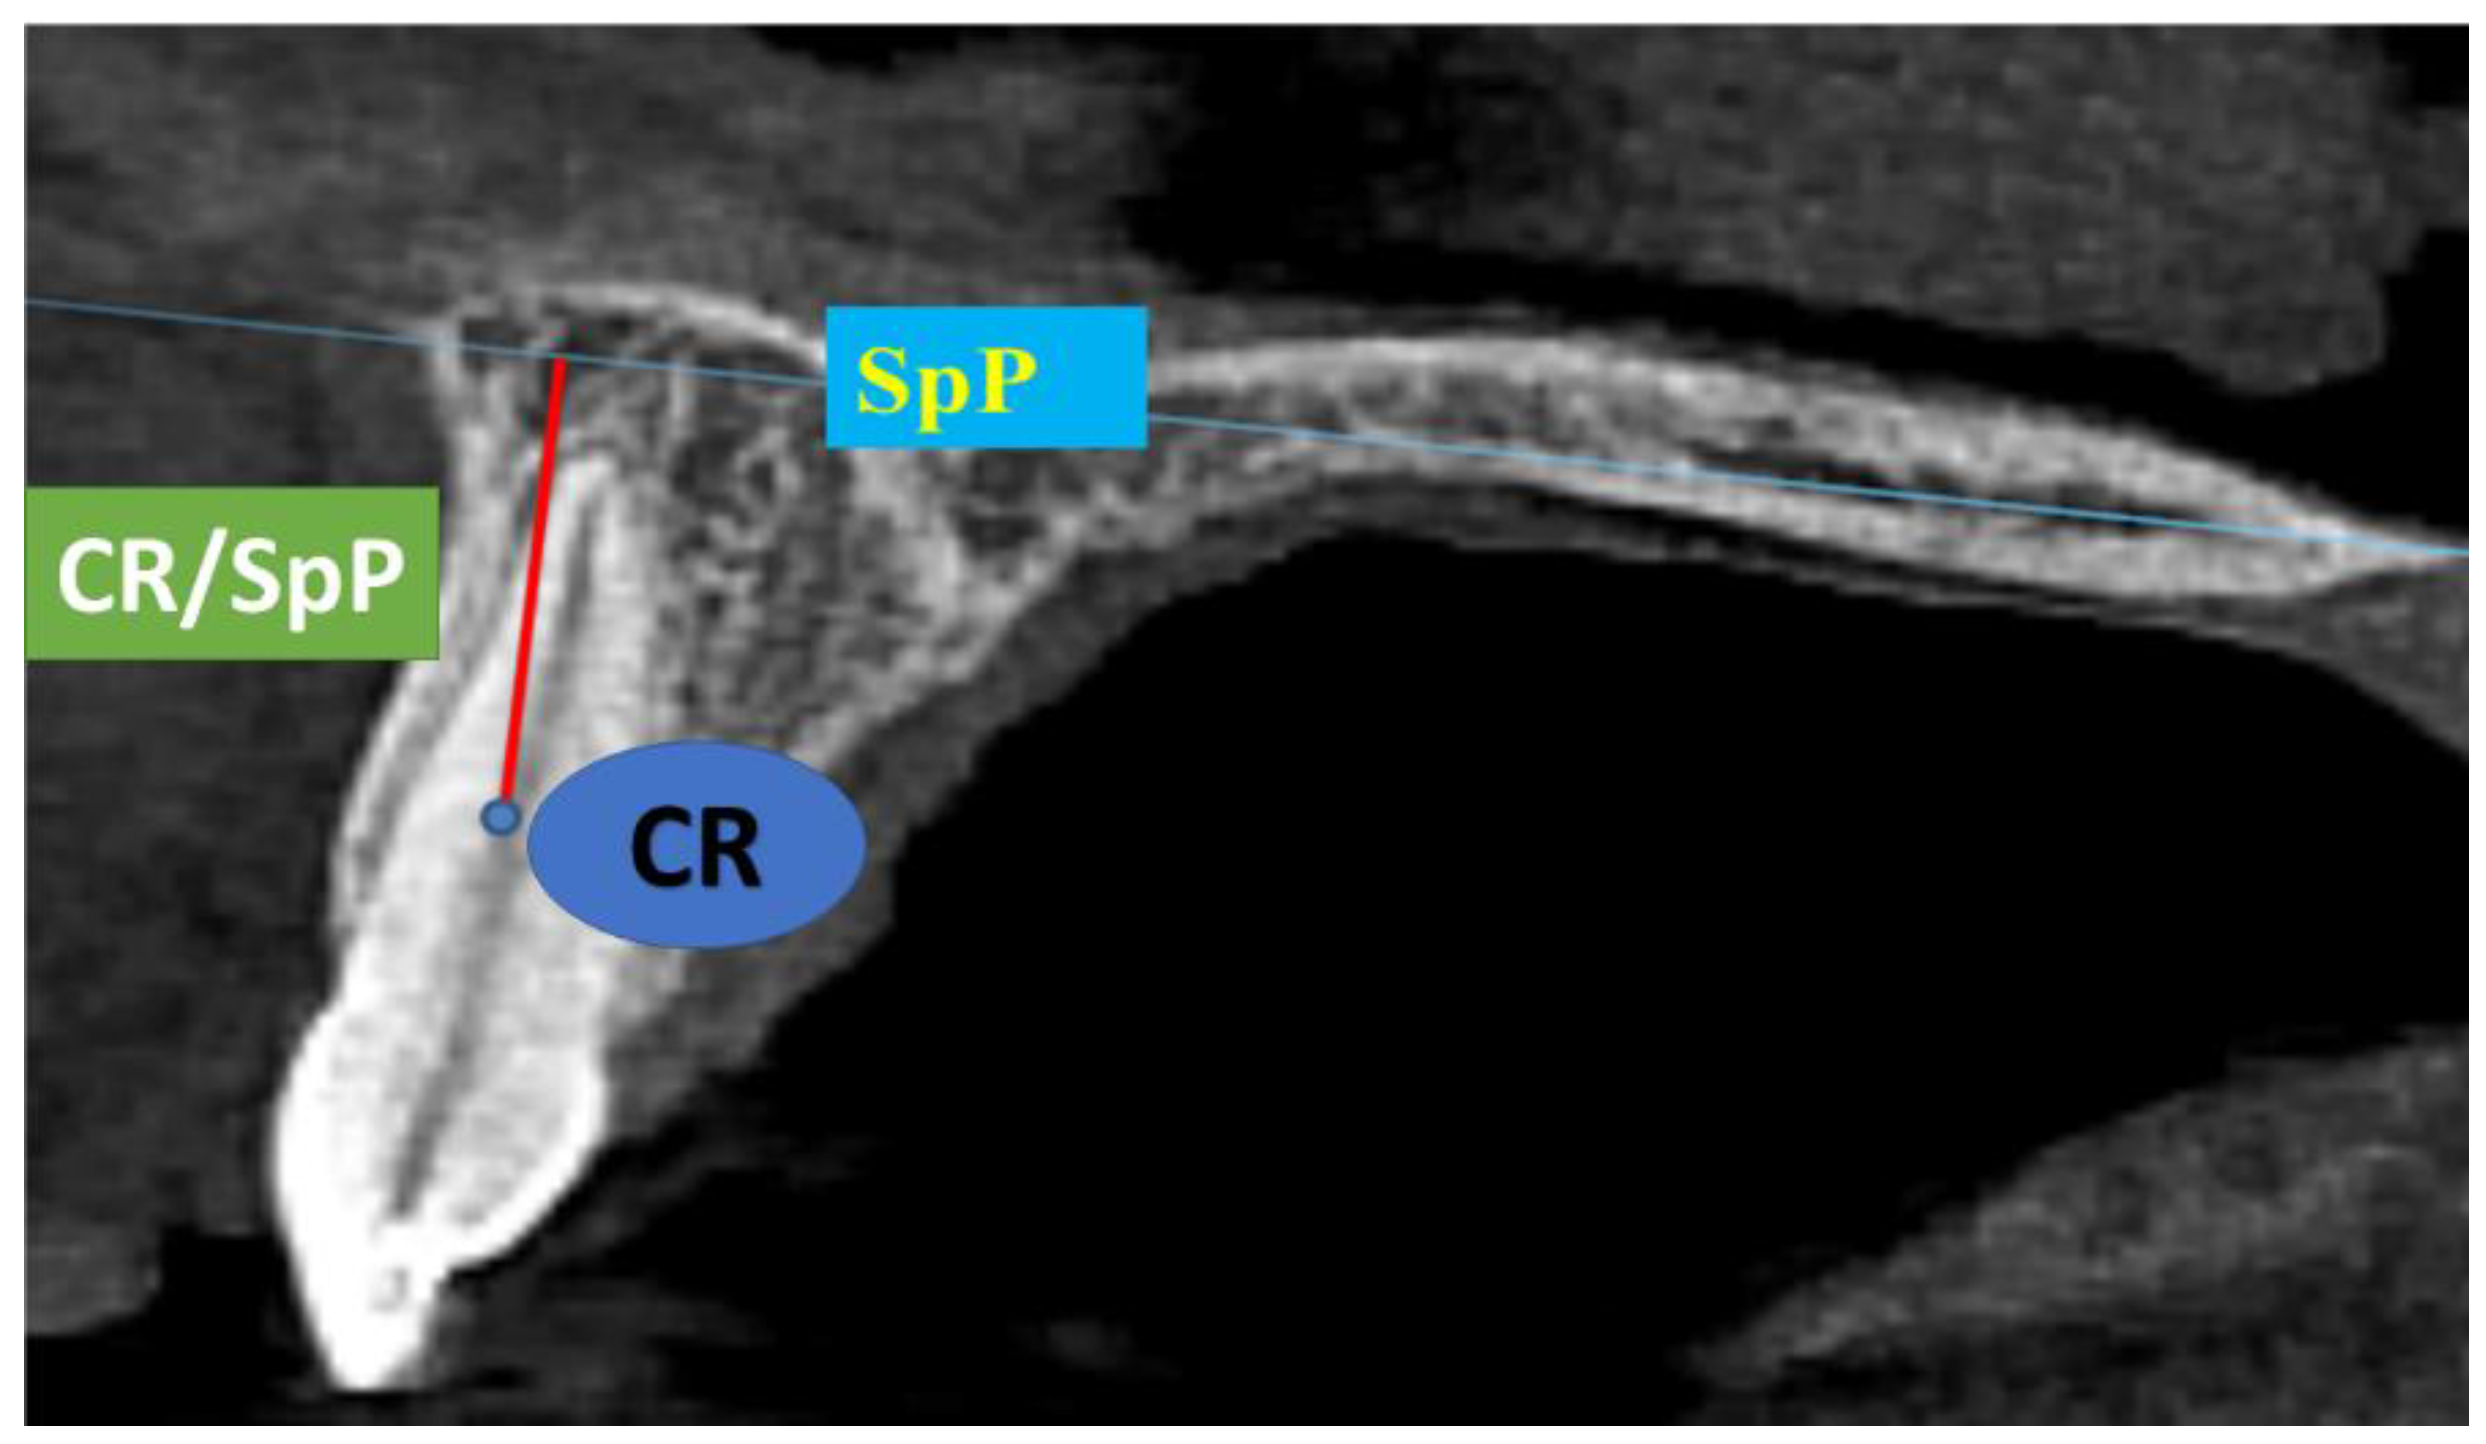

2. Materials and Methods

- Shortest distance from the tip of the cusp or incisal edge of the tooth to the mucogingival line—MGJT (Figure 2). The mucogingival line was determined via the visual method using 10% Lugol’s iodine solution (Figure 2). Keratinized gingiva does not contain glycogen in the surface layers, so there should be no positive iodine reaction and no change in color [22,23];

- Shortest distance from the edge of the gingival margin to the mucogingival junction—KG (width of keratinized gingiva) (Figure 2);

- Papilla height, i.e., the shortest distance from the top of the mesial and distal papillae to the line connecting the marginal gingiva of two adjacent teeth—MP (mesial papillae) and DP (distal papillae) (Figure 2);